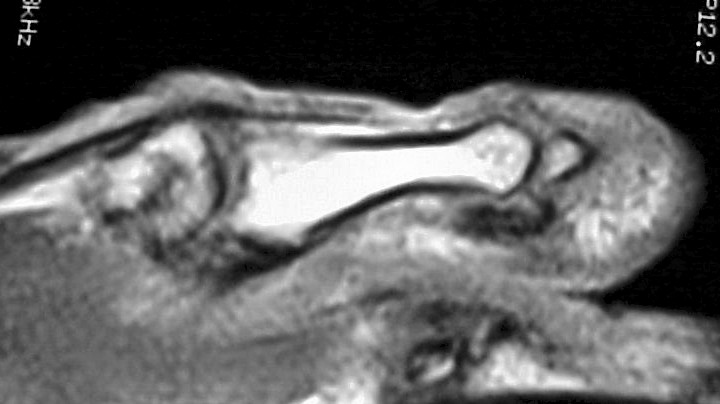

MRI demonstrated ill defined soft tissue replacement of the majority of the distal phalanx:

With contrast enhancement of the transformed area: